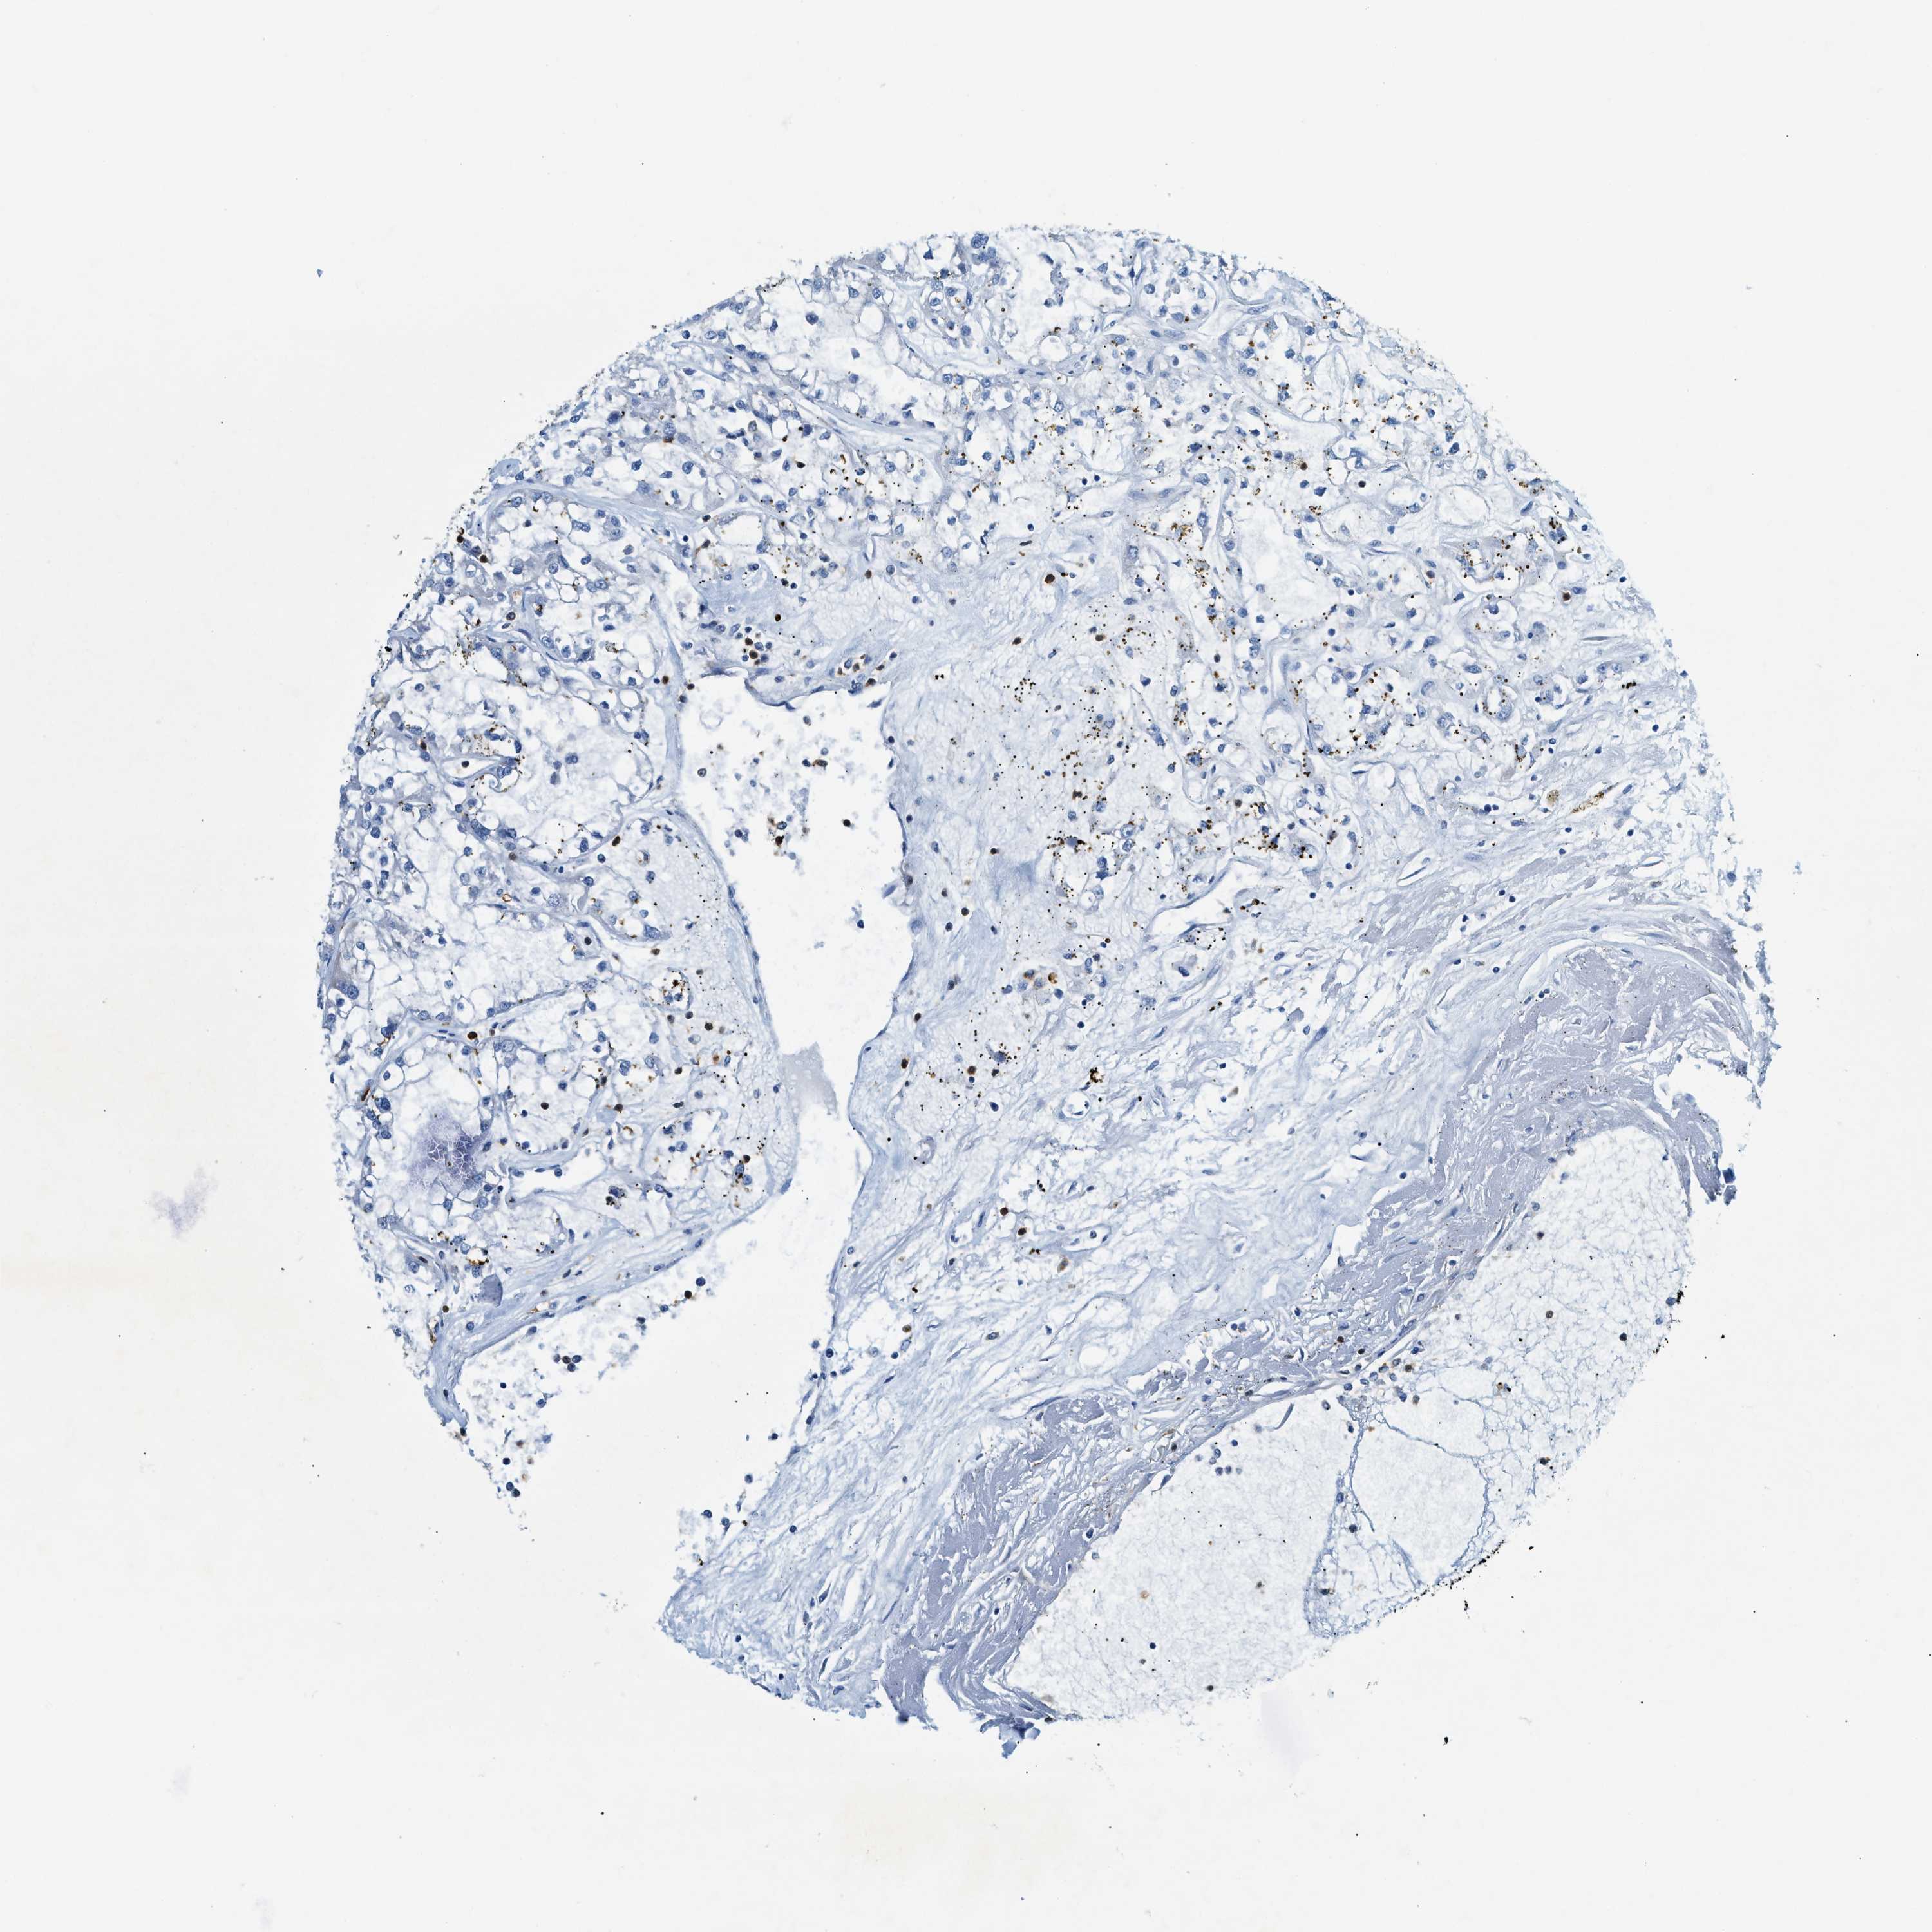

KIDNEY RENAL CLEAR CELL CARCINOMA (VALIDATION) - Interactive survival scatter ploti

ZDHHC13 is not prognostic in Kidney Renal Clear Cell Carcinoma (validation)

: 11.34

Average pTPM 13.9

Number of samples 100